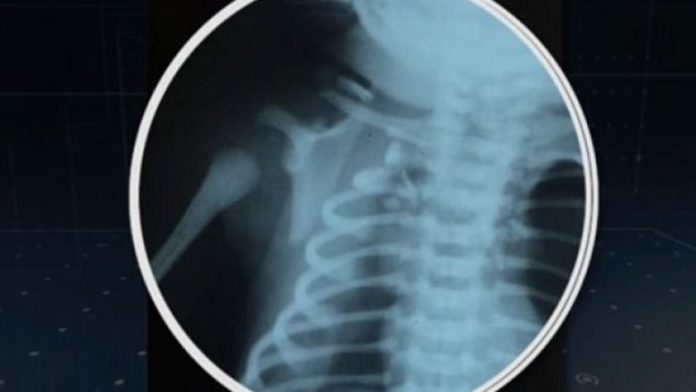

Fëmija që u plagos ende pa lindur

Vogëlushi që u quajt Arthur, kishte marrë lëndime në mushkëri dhe palcën kurrizore, si dhe i është dëmtuar njëri vesh.